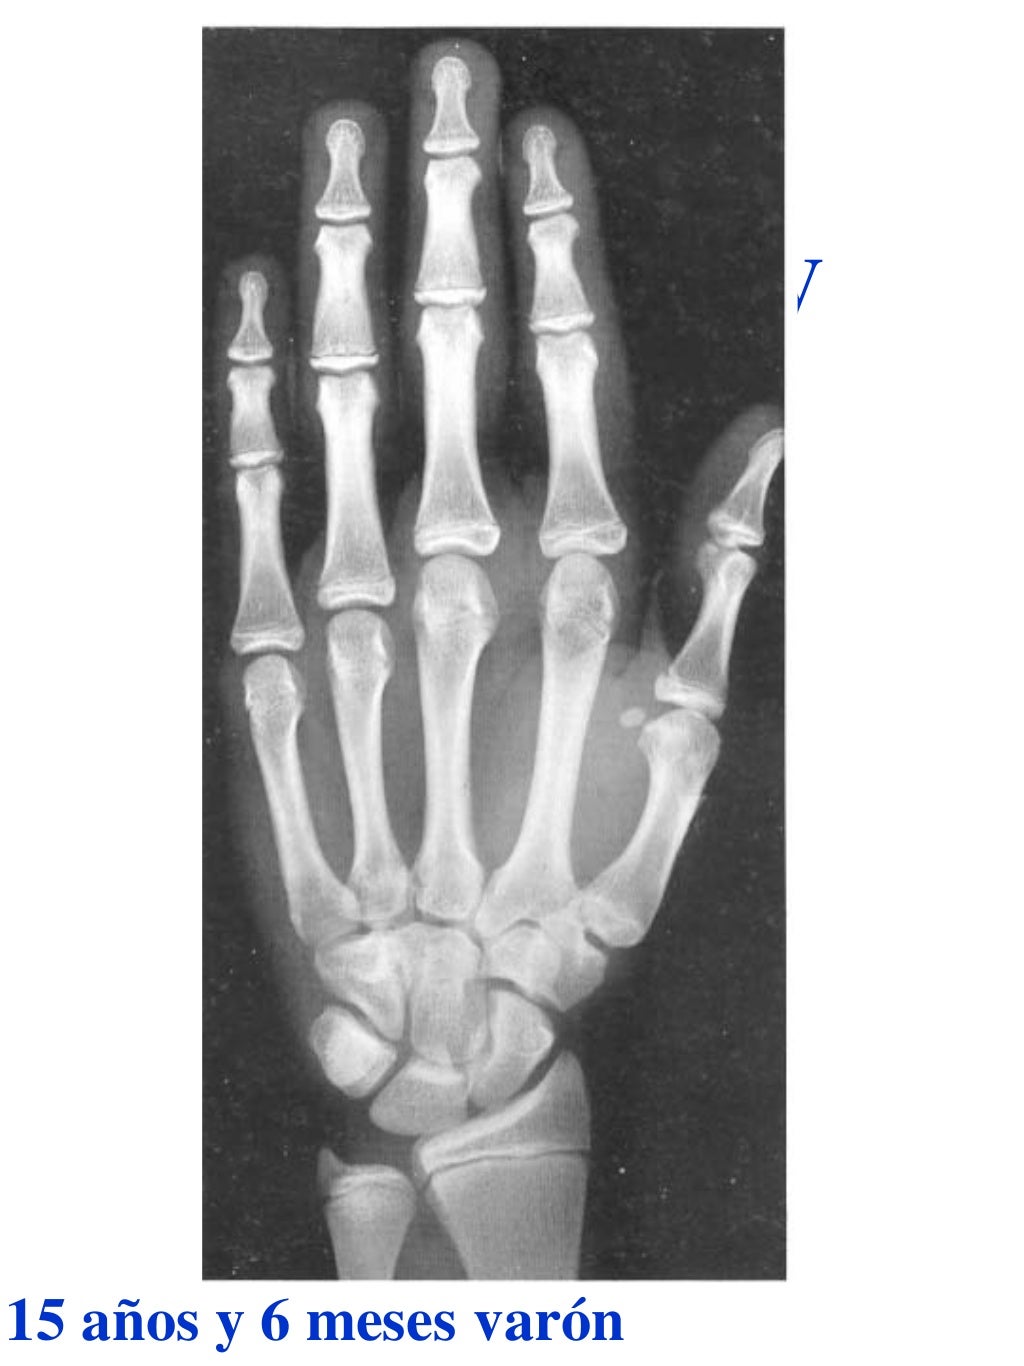

Tablas De Greulich Y Pyle . Scribd is the world's largest social reading and publishing site. This systematic review summarizes the. The radiographic atlas of skeletal development of the hand and wrist by ww greulich and si pyle is a classic radiological. The standards established by greulich and pyle, undoubtedly the most popular method, consist of two series of standard plates. The greulich and pyle method is one of the two main ways to assess the bone age of children. El documento lista las edades. Both main methods of bone age. 153 recomendaciones • 616,869 vistas. Atlas greulich y pyle | pdf | descarga gratuita. The greulich and pyle atlas is used to estimate the age of children and adolescents.

Tablas De Greulich Y Pyle The standards established by greulich and pyle, undoubtedly the most popular method, consist of two series of standard plates. The standards established by greulich and pyle, undoubtedly the most popular method, consist of two series of standard plates. El documento lista las edades. This systematic review summarizes the. The greulich and pyle method is one of the two main ways to assess the bone age of children. Both main methods of bone age. Scribd is the world's largest social reading and publishing site. 153 recomendaciones • 616,869 vistas. Atlas greulich y pyle | pdf | descarga gratuita. The greulich and pyle atlas is used to estimate the age of children and adolescents. The radiographic atlas of skeletal development of the hand and wrist by ww greulich and si pyle is a classic radiological.